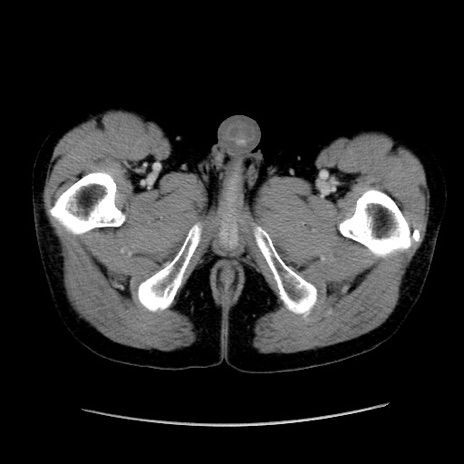

症例37(横断像)

【症例】40歳代 男性

【主訴】腹痛

【現病歴】4時間ほど前に電車に乗車中に臍部上より腹痛出現。徐々に増悪し起立困難となり、救急外来受診。生ものは数日食べていない。今朝お雑煮を食べた。

【身体所見】BT 36.8℃、BP 117/84mmHg、HR 91/min、SpO2 97%、苦悶様、腹部:臍上部広範囲圧痛あり、反跳痛±

【データ】WBC 8100、CRP 0.03